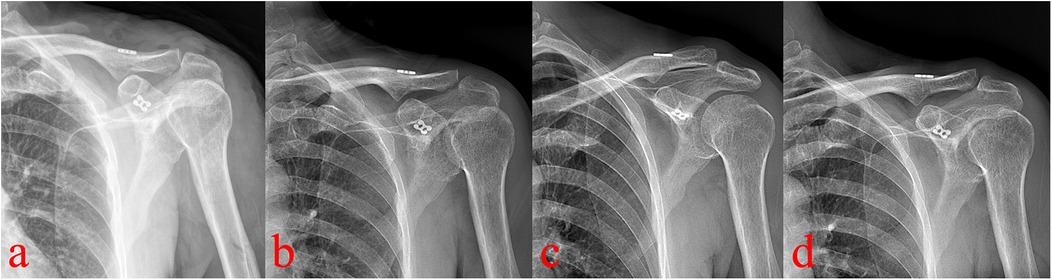

Pain decreased from a VAS score of 6 preoperatively to 2 on day three, and to 0 at three months. At one year, the Constant-Murley score was 98. Tunnel enlargement was observed at 3 months, progressed slightly by 6 months, and stabilized thereafter without clinical consequence. At the 1-year follow-up, the clavicle tunnel showed no further widening compared with the 6-month findings. A minor loss of acromioclavicular joint reduction was noted, and the patient remained asymptomatic with good functional recovery (Figure 4). The Constant-Murley score reached 98, and serial radiographs confirmed reduction of the AC joint without redislocation or complications such as clavicular or coracoid fractures.

Figure 4

Four X-ray images labeled a through d show a shoulder joint with visible surgical hardware, including screws and plates, affixed to the clavicle and shoulder joint. Each image displays slightly different angles and positions of the shoulder. Attention to the hardware's position and surrounding bone structure is evident, focusing on post-surgical alignment and healing.

Figure 4. Postoperative radiographs (a–d, immediate postoperative, 3-month, 6-month, and 1-year) show progressive clavicular tunnel enlargement until 6 months, then stabilization, with no coracoid tunnel widening. A minor loss of AC joint reduction observed.